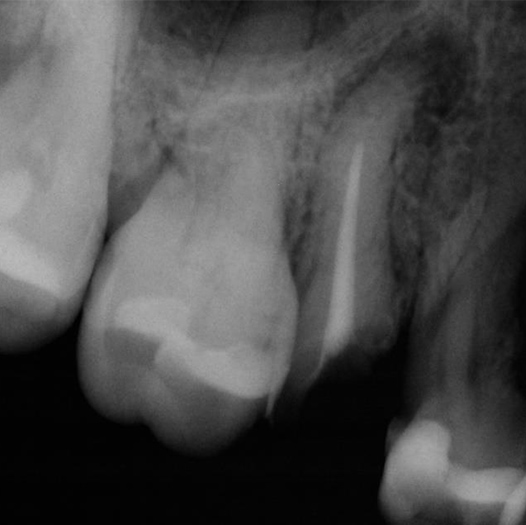

Before

After

Before Root Canal treatment

After Root Canal treatment